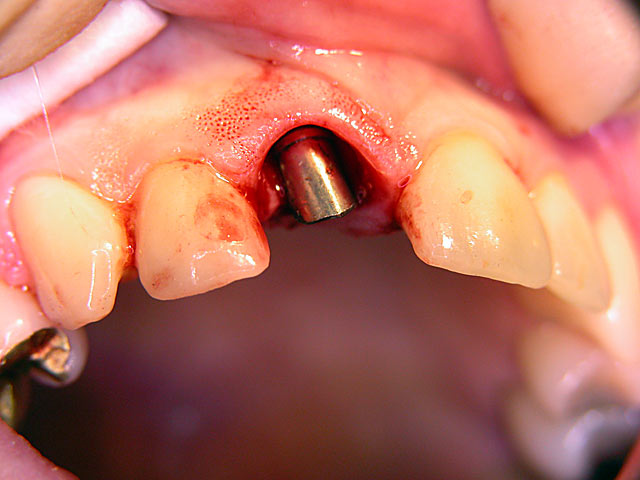

Frontzahn-Implantation: